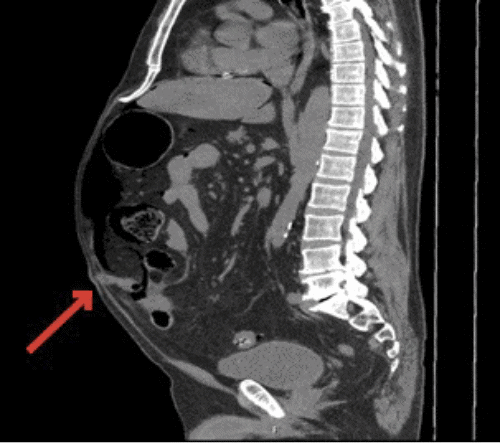

Figure 1. CT Scans Demonstrating Meckel's Diverticulum. Published with Permission

B) sagittal view with Meckel’s diverticulum present in umbilical hernia (arrow)

A 67-year-old man presented to the emergency department with the chief complaint of worsening abdominal pain, nausea, and vomiting over the course of one day. The patient reported some mild heavy lifting the day before but had minimal pain, with a new bulge noted near his umbilicus. On physical exam, the patient was found to have a very distended abdomen with focal tenderness in the periumbilical region. The patient's CT scan showed a large amount of free air with a small umbilical hernia. Before taking the patient to the OR, he asked, "Could I have a Meckel's diverticulum causing my problems? My son had this same surgery performed two years ago. He had a bleeding Meckel's diverticulum."